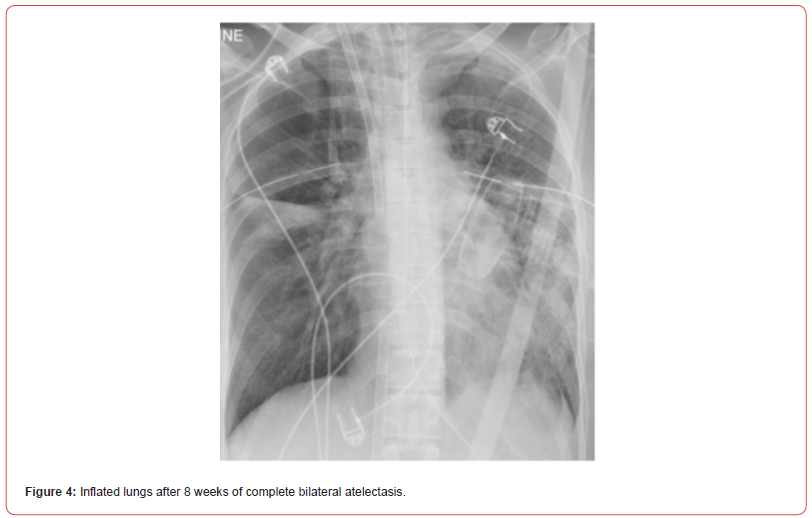

Eight weeks after the patient’s crisis, bronchoscopy with cryoprobe to freeze and pull blood clots from the airways followed by immediate argon plasma coagulation (APC) of remaining bleeding mucosal vessels were used. Following this procedure, the patient was ventilated with gradual increase of tidal volumes, and after 8 weeks of complete bilateral complete atelectasis, chest X-ray revealed both lungs inflation (figure 4). In the following days, the patient’s kidneys recovered and she was gradually weaned off the VV-ECMO and mechanical ventilation. Unfortunately, she suffered from severe upper and lower digital ischemia, presumably due to multiple etiologies: prolonged septic shock, prolonged VV-ECMO with no anti-coagulation due to ongoing bleeding, and probably from usage of intravenous and inhalational hexacaprone that was given as a salvage therapy to control the ongoing bleeding. Eventually, the digital ischemia required amputation of distal phalanx in both hands and anterior soles. Other than that, the patient recovered with no need of supplemental oxygen and preserved cognitive function and was discharged to a rehabilitation institute. Since then, there were no new events of hemoptysis so far (18 months).